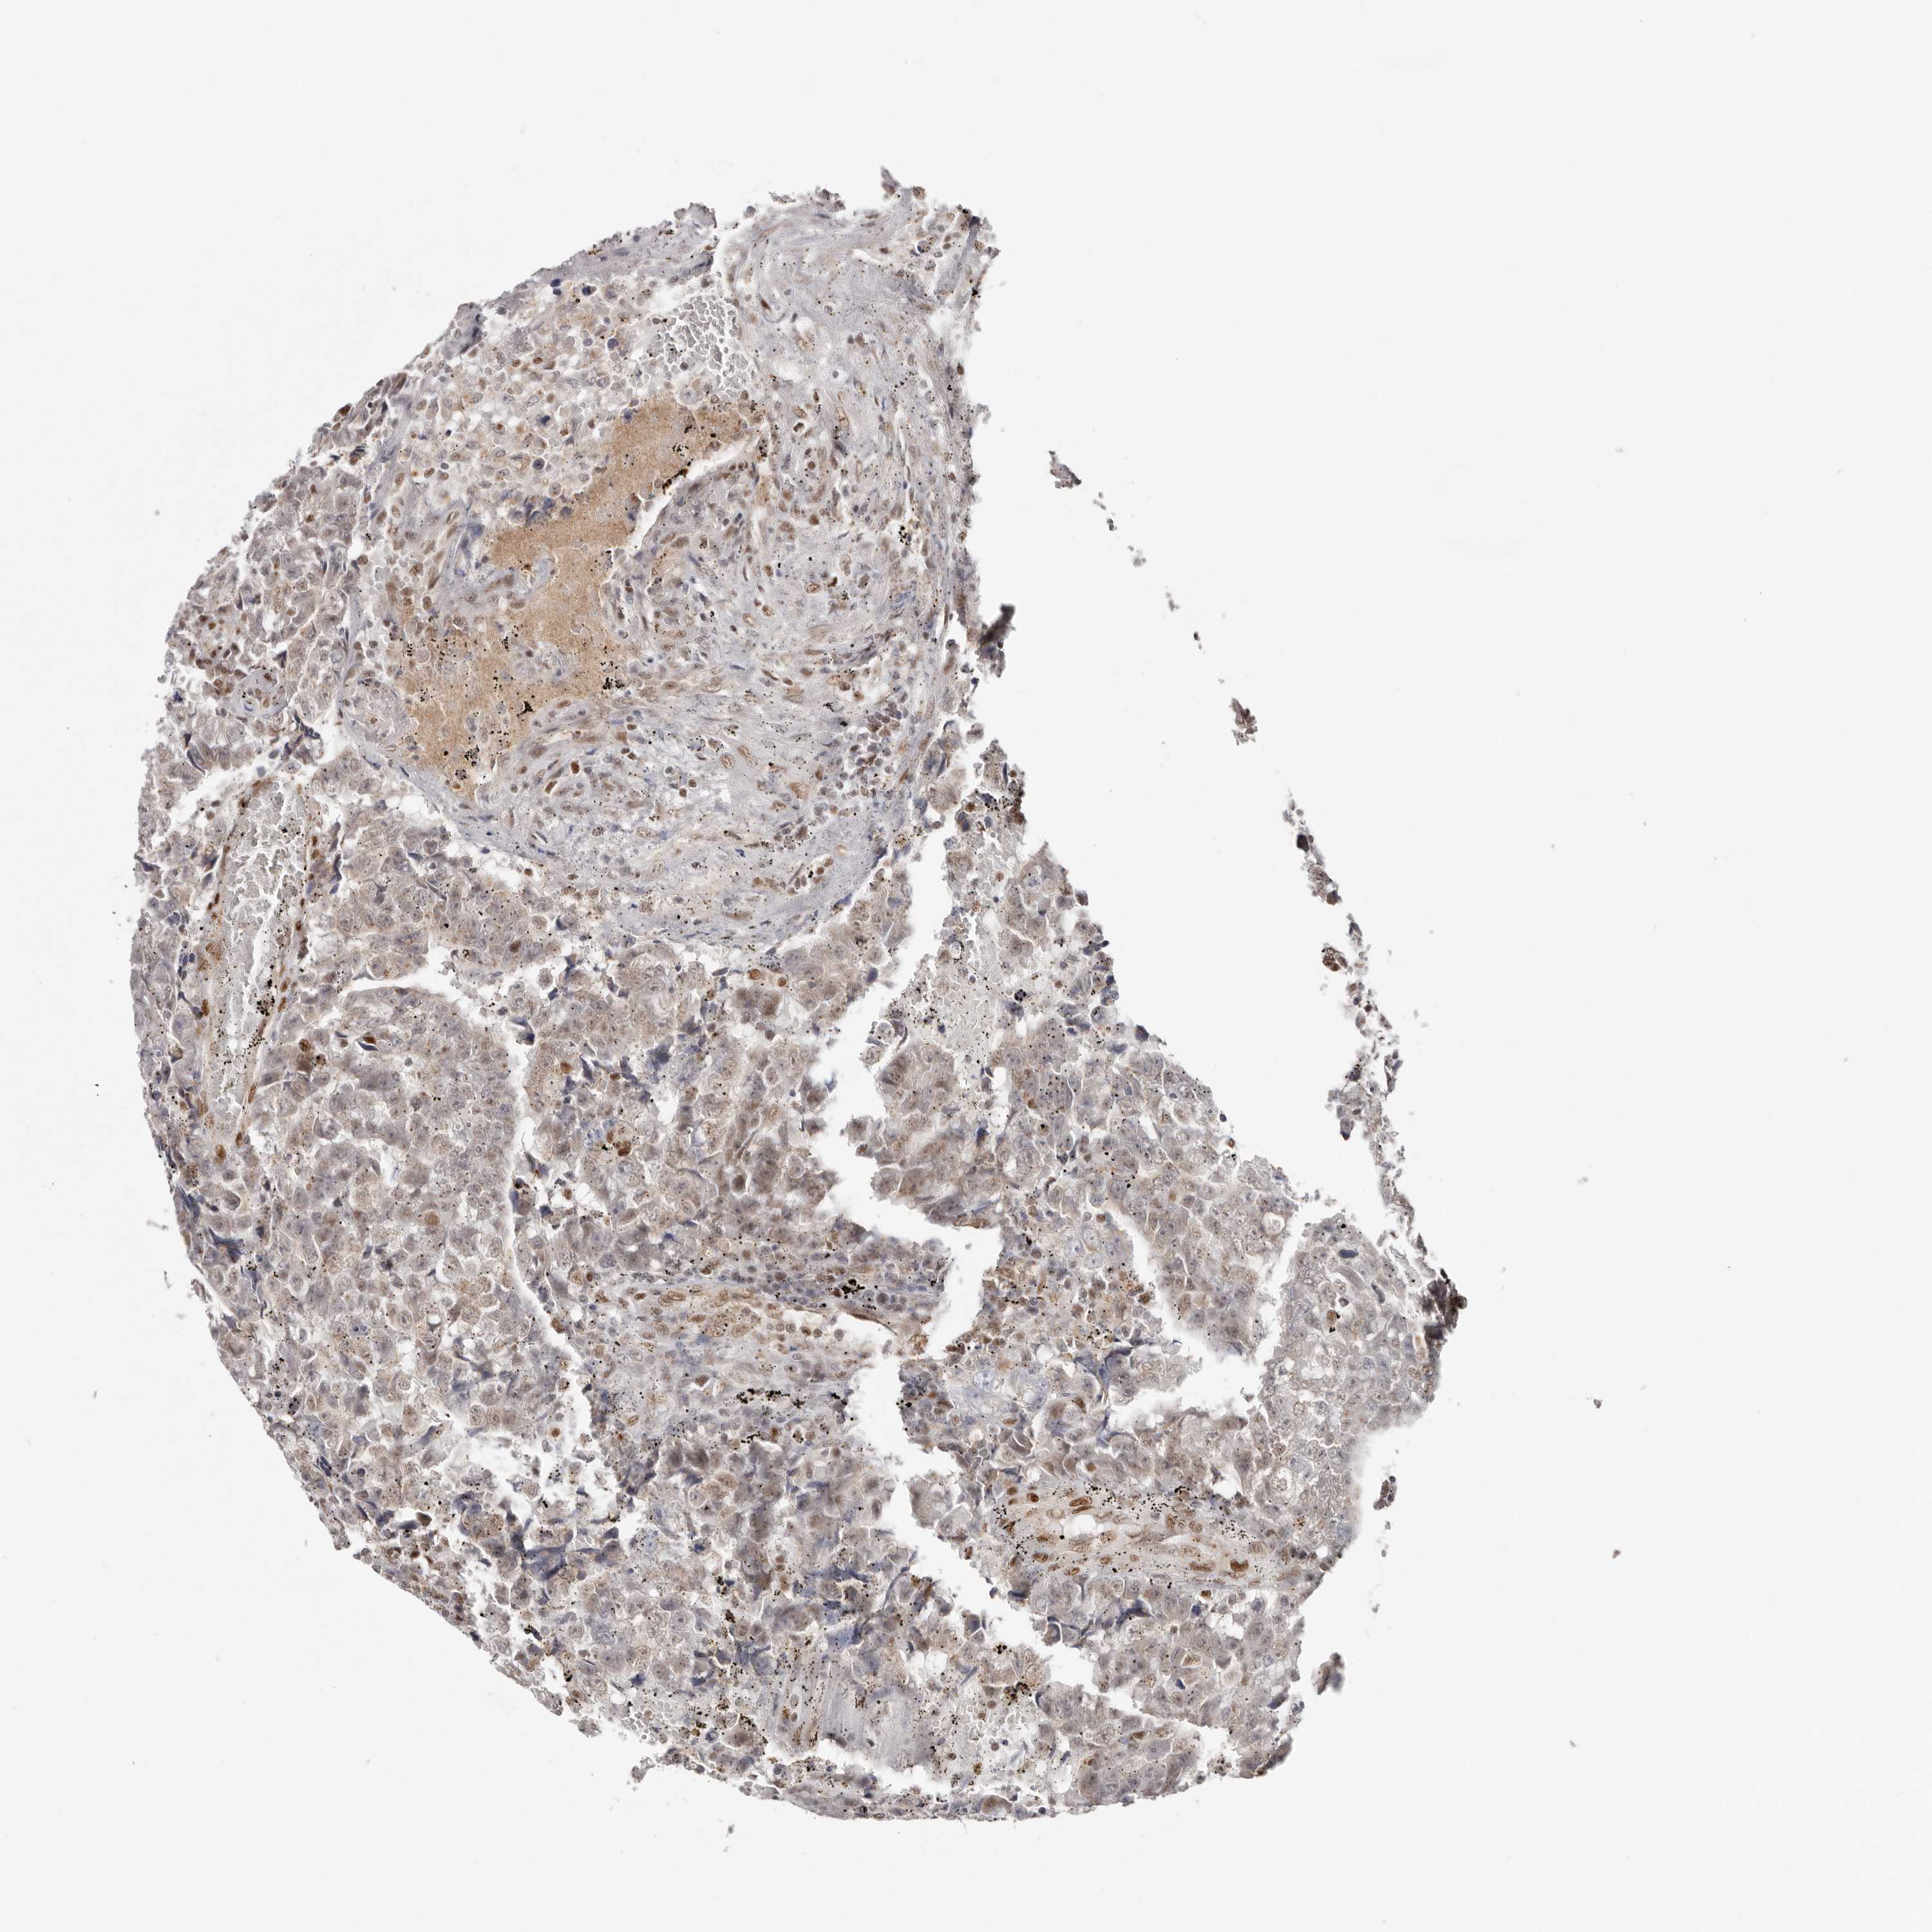

TESTIS CANCER - Protein expressioni

A mouse-over function shows sample information and annotation data. Click on an image to view it in a full screen mode. Samples can be filtered based on level of antibody staining by selecting one or several of the following categories: high, medium, low and not detected. The assay and annotation is described here.

Note that samples used for immunohistochemistry by the Human Protein Atlas do not correspond to samples in the TCGA dataset.

Antibody stainingi

Antibody staining in the annotated cell types in the current human tissue is reported as not detected, low, medium, or high, based on conventional immunohistochemistry profiling in selected tissues. This score is based on the combination of the staining intensity and fraction of stained cells.

Each image is clickable and will lead to virtual microscopy that enables deeper exploration of all samples and also displays staining intensity scores, fraction scores and subcellular localization as well as patient and tissue information for each sample.

Antibody HPA028897

Carcinoma, Embryonal, NOS